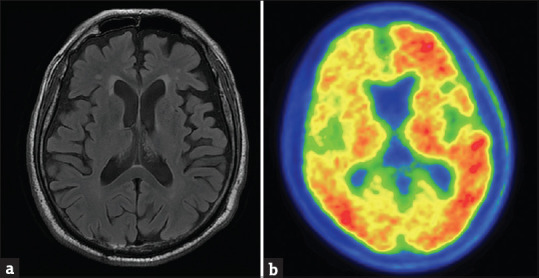

Abstract Image